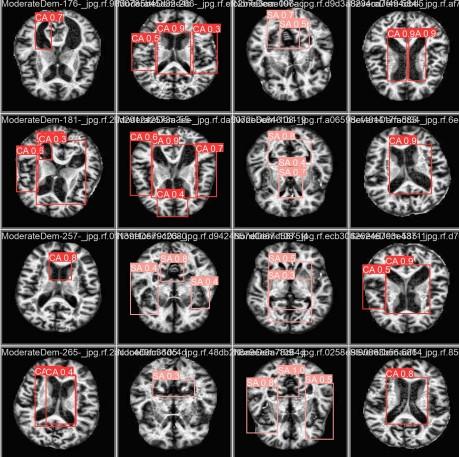

Imagem mostra cérebro visto por meio de exame de ressonância magnética.

Legenda: Conjunto de imagens de ressonância magnética cerebral, mostrando diferentes seções e angulações do cérebro humano.

Foto: Reprodução/Estudo IFCE.

A análise detalhada das imagens de RM, incluindo a anotação de regiões com possíveis alterações cerebrais, “possibilitou uma avaliação minuciosa das modificações induzidas pela Doença de Alzheimer”, destacam os alunos, em documento assinado coletivamente.

Segundo Michael, a máquina analisa os exames de imagem e informa uma porcentagem de correspondência daqueles resultados para Alzheimer. “Ela reduz o espaço amostral de possibilidades, pra que o médico possa tomar a melhor decisão.”

“A segmentação de imagens demonstrou ser uma ferramenta essencial para o diagnóstico e monitoramento da doença, pois permite a extração de características relevantes e a quantificação do progresso das atrofias em estruturas específicas”, pontuam.

Os alunos reforçam que “a identificação precoce das alterações é considerada essencial para o manejo eficaz da doença, possibilitando intervenções terapêuticas mais oportunas”. Para isso, “o desenvolvimento de métodos automáticos de segmentação contribui para a análise quantitativa e para o apoio ao diagnóstico da doença”.

“A IA explicável vem pra tornar o resultado legível e entendível, pra que o médico entenda o porquê de a IA ter tomado essa decisão, por que ela identificou que esse ponto pode vir a ser Alzheimer no futuro”, diz o professor.